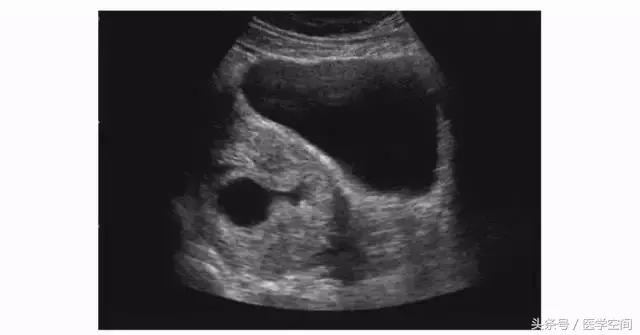

又分为两种类型,第一种为宫腔内见孕囊型,孕囊多位于宫腔下段(较大孕囊可充满整个宫腔),但孕囊部分种植于剖宫产子宫瘢痕处,彩色多普勒超声(CDFI)检查瘢痕部位常可见较丰富血流信号(见图2);第二种为瘢痕部位包块型,子宫剖宫产瘢痕处未见孕囊,可见不均质低回声包块,其周边常可见较丰富血流信号(见图3)。不典型CSP容易漏诊及误诊。

图2不典型CSP的超声表现